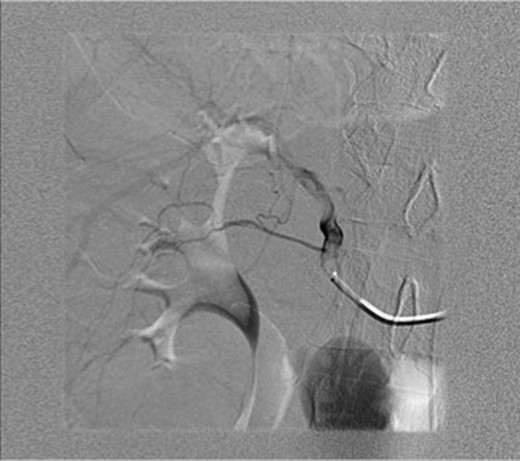

An ultrasound was done showing a mass in the right upper quadrant with no visualization of the gallbladder and no evidence of biliary tree dilatation. Therefore, a CT scan was performed which showed a large haematoma in the gallbladder fossa, which distends the gallbladder wall causing mass effect (Fig. 1a and b). Furthermore, active extravasation of IV contrast was seen. Initially, this was not clear if the haematoma is arising from the liver or within the gallbladder. Given his haemodynamic stability he was taken to the interventional angiography suite for an arteriogram of his abdominal aorta and splanchnic vessels. The bleeding was localized to a branch of the cystic artery and no pseudoaneurysm was identified (Fig. 2). Then, embolization of cystic artery with gelfoam material was performed. Since, embolization of the cystic artery proper was done, the decision was made to explore the patient and perform a cholecystectomy. Prior to the operation the patient became tachycardic at 100 with a systolic blood pressure of 90 and a diastolic of 60. His repeat haemoglobin was 10.1. Appropriate resuscitation with blood transfusion was performed.

Arteriogram of abdominal aorta and splanchnic vessels showing localized bleeding in a branch of the cystic artery and no pseudoaneurysm.